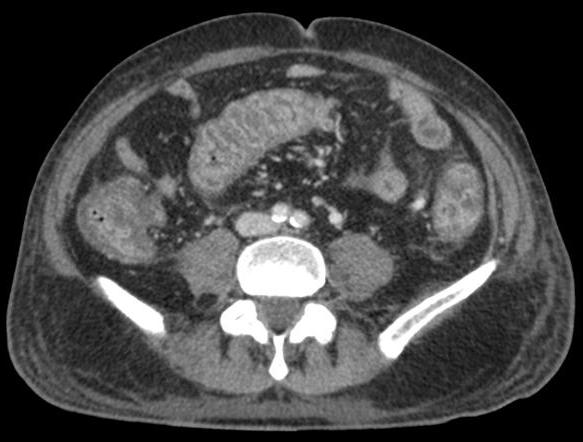

Aspect TDM une colite ischemique est :

lesion segmentaire regionale , Epaissisement de la paroi du

colon en symetrique ou lobulaire , stricture irreguliaire

segmentaire du colon ., oedeme de la muqueuse en forme signe

de cible " target sign ", presente de gas intramurale ou a

la veine porte , thrombus de artere ou veine mesenterique

superieur .

Aspect TDM une colite

ischemique avec image de gas intramurale du colon

sigmoide . Image radiologique TDM en coupe axiale a

travers sacrum S2 |

|

La presence de

gas au systeme portal intra hepatique dans colite

ischemique . Inmage radiologique TDM en coupe axiale |